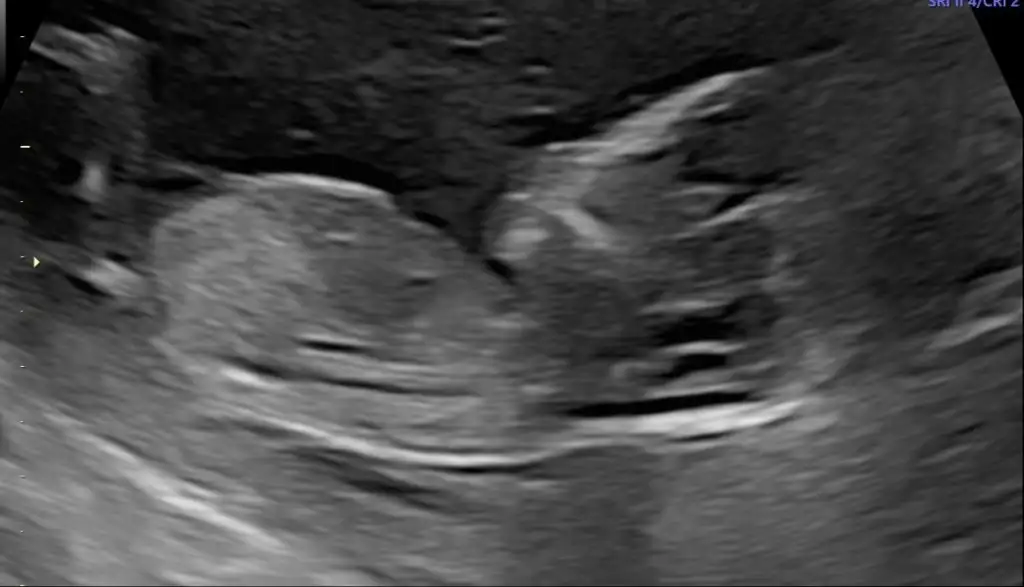

Nubu görünmüyorCanim benimkine de bakarmisin

Merhaba bende meraktan buralardayımvakit ayırabilirseniz birde bizim tahminde bulunabilirmisiniz

Yükledim hepsini şimdi canım. Nub görünen foto da var.Emin değilim ama sanki erkek gibi başka USG varsa paylaşın

Buna da bakabilir misiniz yarın yeni kontrolüm var bakalım doktor nediyecekNubu görünmüyor